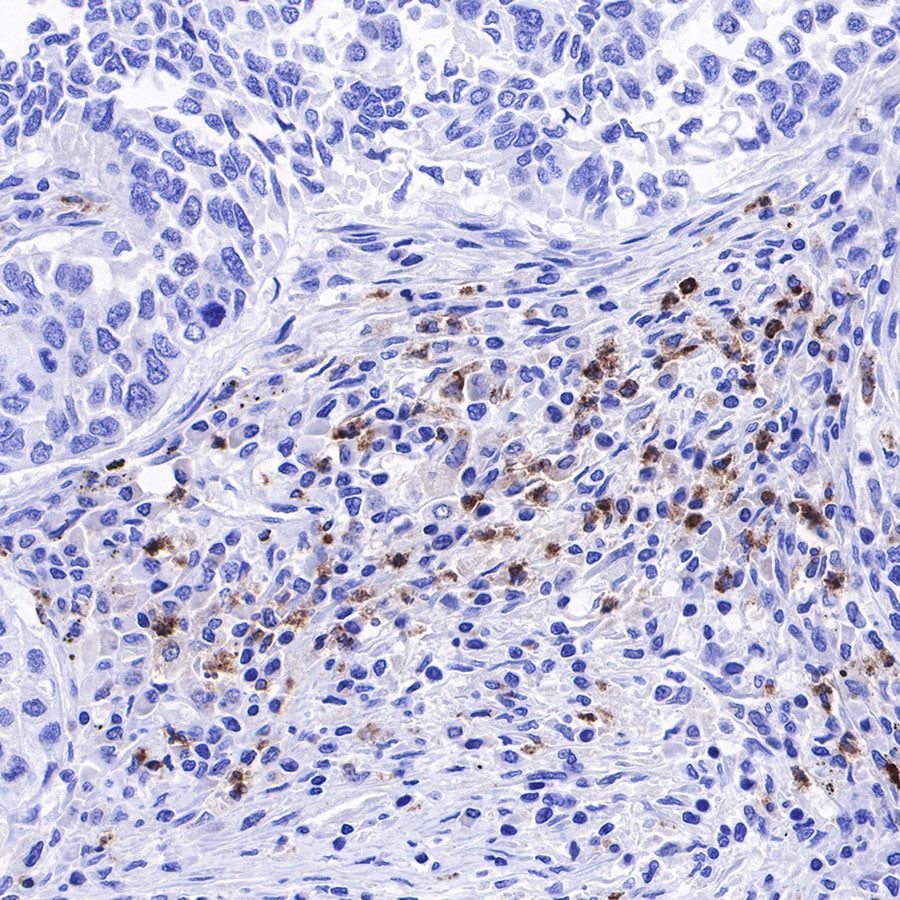

IHC shows positive staining in paraffin-embedded human spleen. Anti-Lysozyme antibody was used at 1/100 dilution, followed by a HRP Polymer for Mouse & Rabbit IgG (ready to use). Counterstained with hematoxylin. Heat mediated antigen retrieval with Tris/EDTA buffer pH9.0 was performed before commencing with IHC staining protocol.